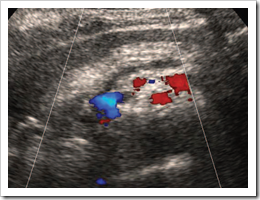

Ultrasound images Chronic pancreatitis

The pancreas becomes abnormally hyperechoic (Fig. A). This should not be confused with the normal increase in echogenicity with age. The gland may be atrophied and lobulated and the main pancreatic duct is frequently dilated and ectatic, with a beaded appearance.

As with acute inflammation, CT is the method of choice for demonstrating the complications of chronic pancreatitis. Obstruction of the duct can cause pseudocyst formation, and other complications include biliary obstruction and portal/splenic vein thrombosis.

Fig. A Chronic pancreatitis in a patient with alcoholic cirrhosis the pancreas is hyperechoic compared with

the liver and has a heterogeneous texture with a lobulated outline.